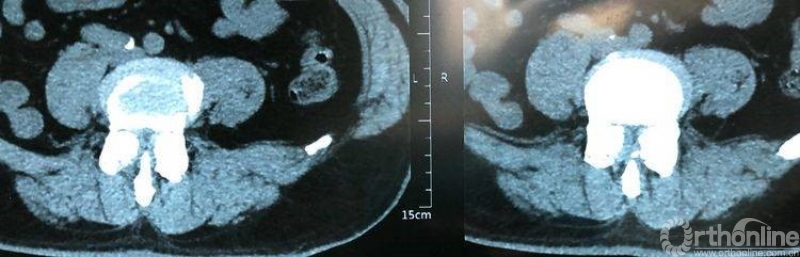

术前CT示L4/5重度椎管狭窄,腰椎滑脱合并硬膜囊受压。辅助检查如下:

术前CT